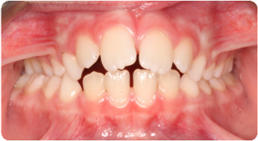

Drag the slider to compare the before and after. This patient presented with severe crowding and overlapping teeth, resolved entirely through BioLign Method-guided aligner treatment.

Overlapping teeth resolved through arch form restoration